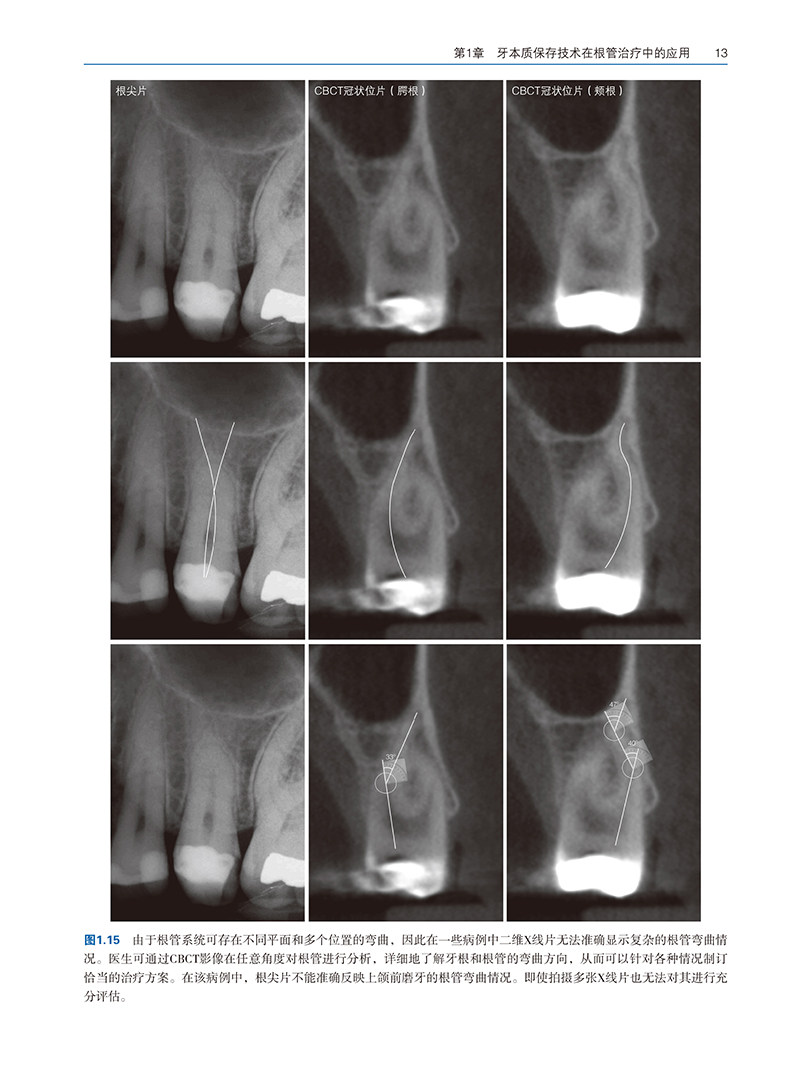

第1章 牙本质保存技术在根管治疗中的应用